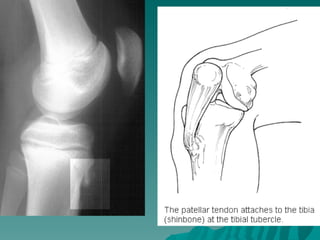

A. Alt ekstremite

   Tüberasitas tibia        Osgood-Schlatter

Osgood-Schlatter Hastalığı:

 Tüberasitas tibianın osteokondrozudur.

Hastalığın, tüberositas tibiaya kuadriseps

kasıyla gelen tekrarlayıcı kuvvetler

sonucu geliştiği düşünülür.

 Erkeklerde ve adolesan çağda daha sıktır.

Bilateral olabilir. Dizin ön tarafında ağrı

olur. Yakınmalar koşma, zıplama,

merdiven çıkma ile artar, Dinlenmekle

geçer.

 Muayenede tüberasitas tibia genişlemiş ve

duyarlıdır.